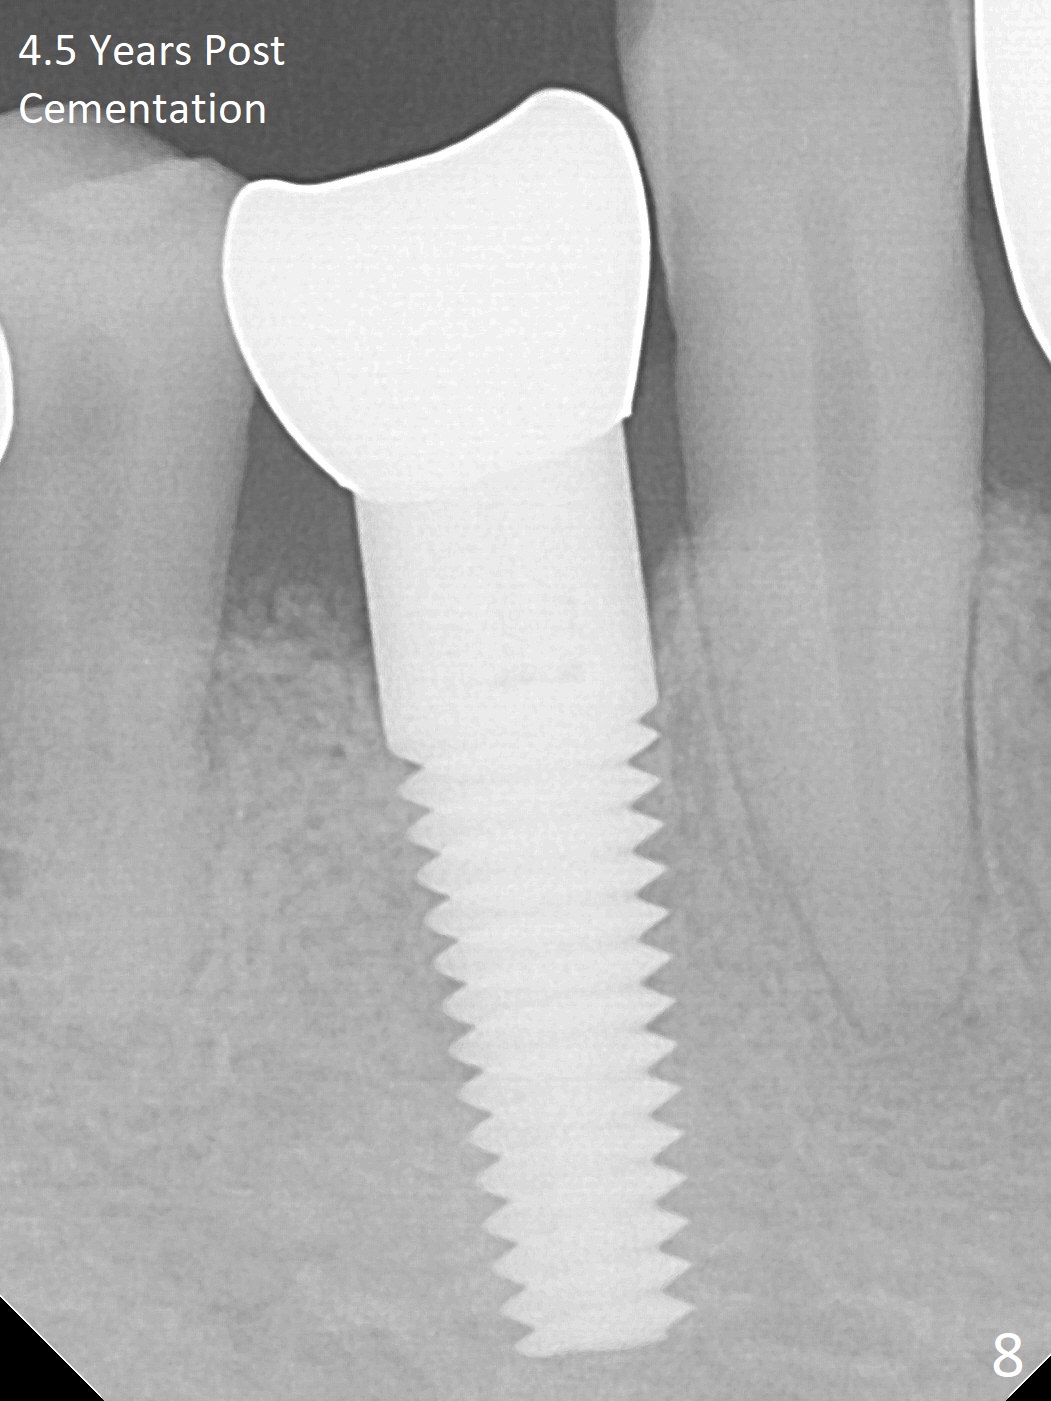

A 66-year-old man has poor dentition (Fig.1). Several teeth (x) including #28 need extraction and implants. The tooth #28 is extracted (Fig.2), followed by immediate implant (5x17 mm, Fig.3 I). There is more buccal gingival recession over the implant (Fig.4), which is less prominent 1.5 months postop (Fig.5). The definitive restoration is delivered less than 2 months postop (Fig.6), because of travel abroad. The patient agrees not to chew with the Emax crown. Five months later, he returns with chipped porcelain (Fig.7 arrowhead). It appears that immediate implant can survive early and over loading. More implants are necessary to share the masticatory loading. Since there is malocclusion, where to place implants appears to be critical (Model 3 30 4 5 6 7). There is no bone loss 4.5 years (Fig.8) or 5 years 8 months (Fig.9) post cementation.